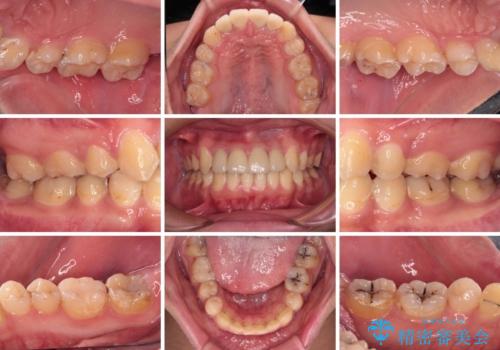

- むし歯が多く、歯並びも悪いとのことで、以前通院されていたご家族の紹介で来院された患者様です。

口腔内に無頓着であったため、まずはしっかりと歯磨きトレーニングを行い、必要な虫歯治療を行いました。

矯正治療は、むし歯が酷く抜歯が望ましい歯を1本抜歯して、ワイヤー装置にて整えることとしました。

矯正治療後は上顎前歯4本をオールセラミッククラウンにて補綴治療を行うこととしました。